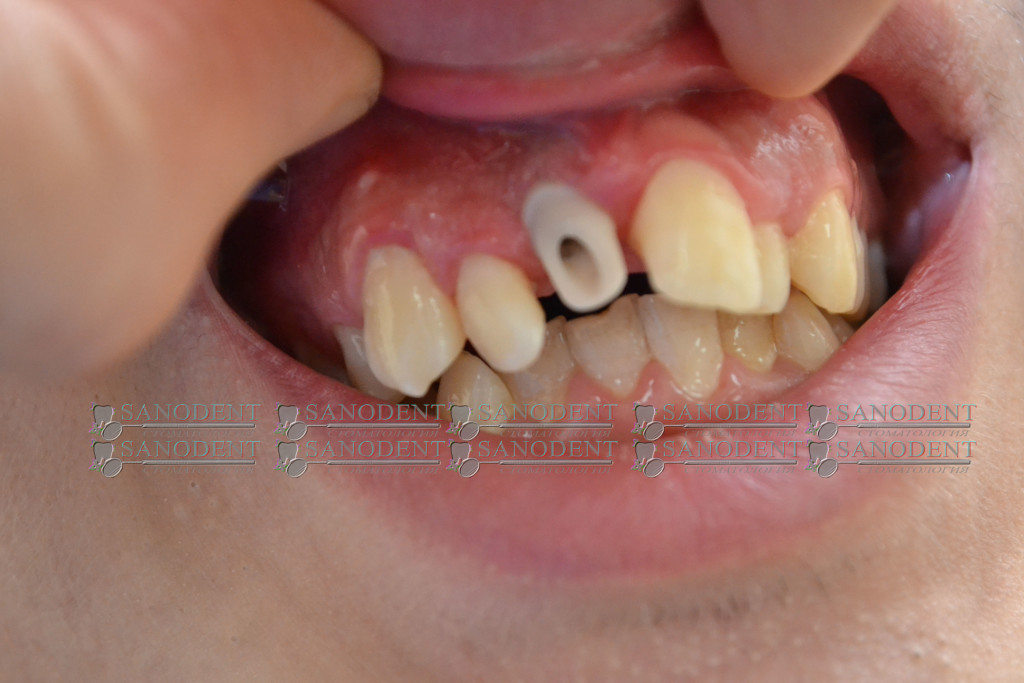

Имплантация, восстановление фронтального зуба с использованием циркониевого абатмента и безметалловой прессованной керамической коронки Е-макс.

- вживленный иплантат

- циркониевый абатмент

- коронка Е-мах